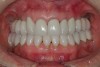

Figure 30  Final restorations.

Figure 30

Figure 31  Technical precision and artistic skill blend into a pleasing smile and a happy patient.

Figure 31